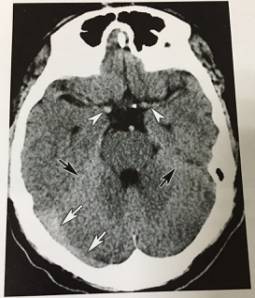

1、正常横窦、小脑幕、大脑中动脉

CT平扫示正常正常横窦(白箭)、小脑幕(黑箭)和大脑中动脉(无尾白箭头),正常人或高血红蛋白血症患者密度可以增高,易误诊为蛛网膜下腔出血或横窦血栓。